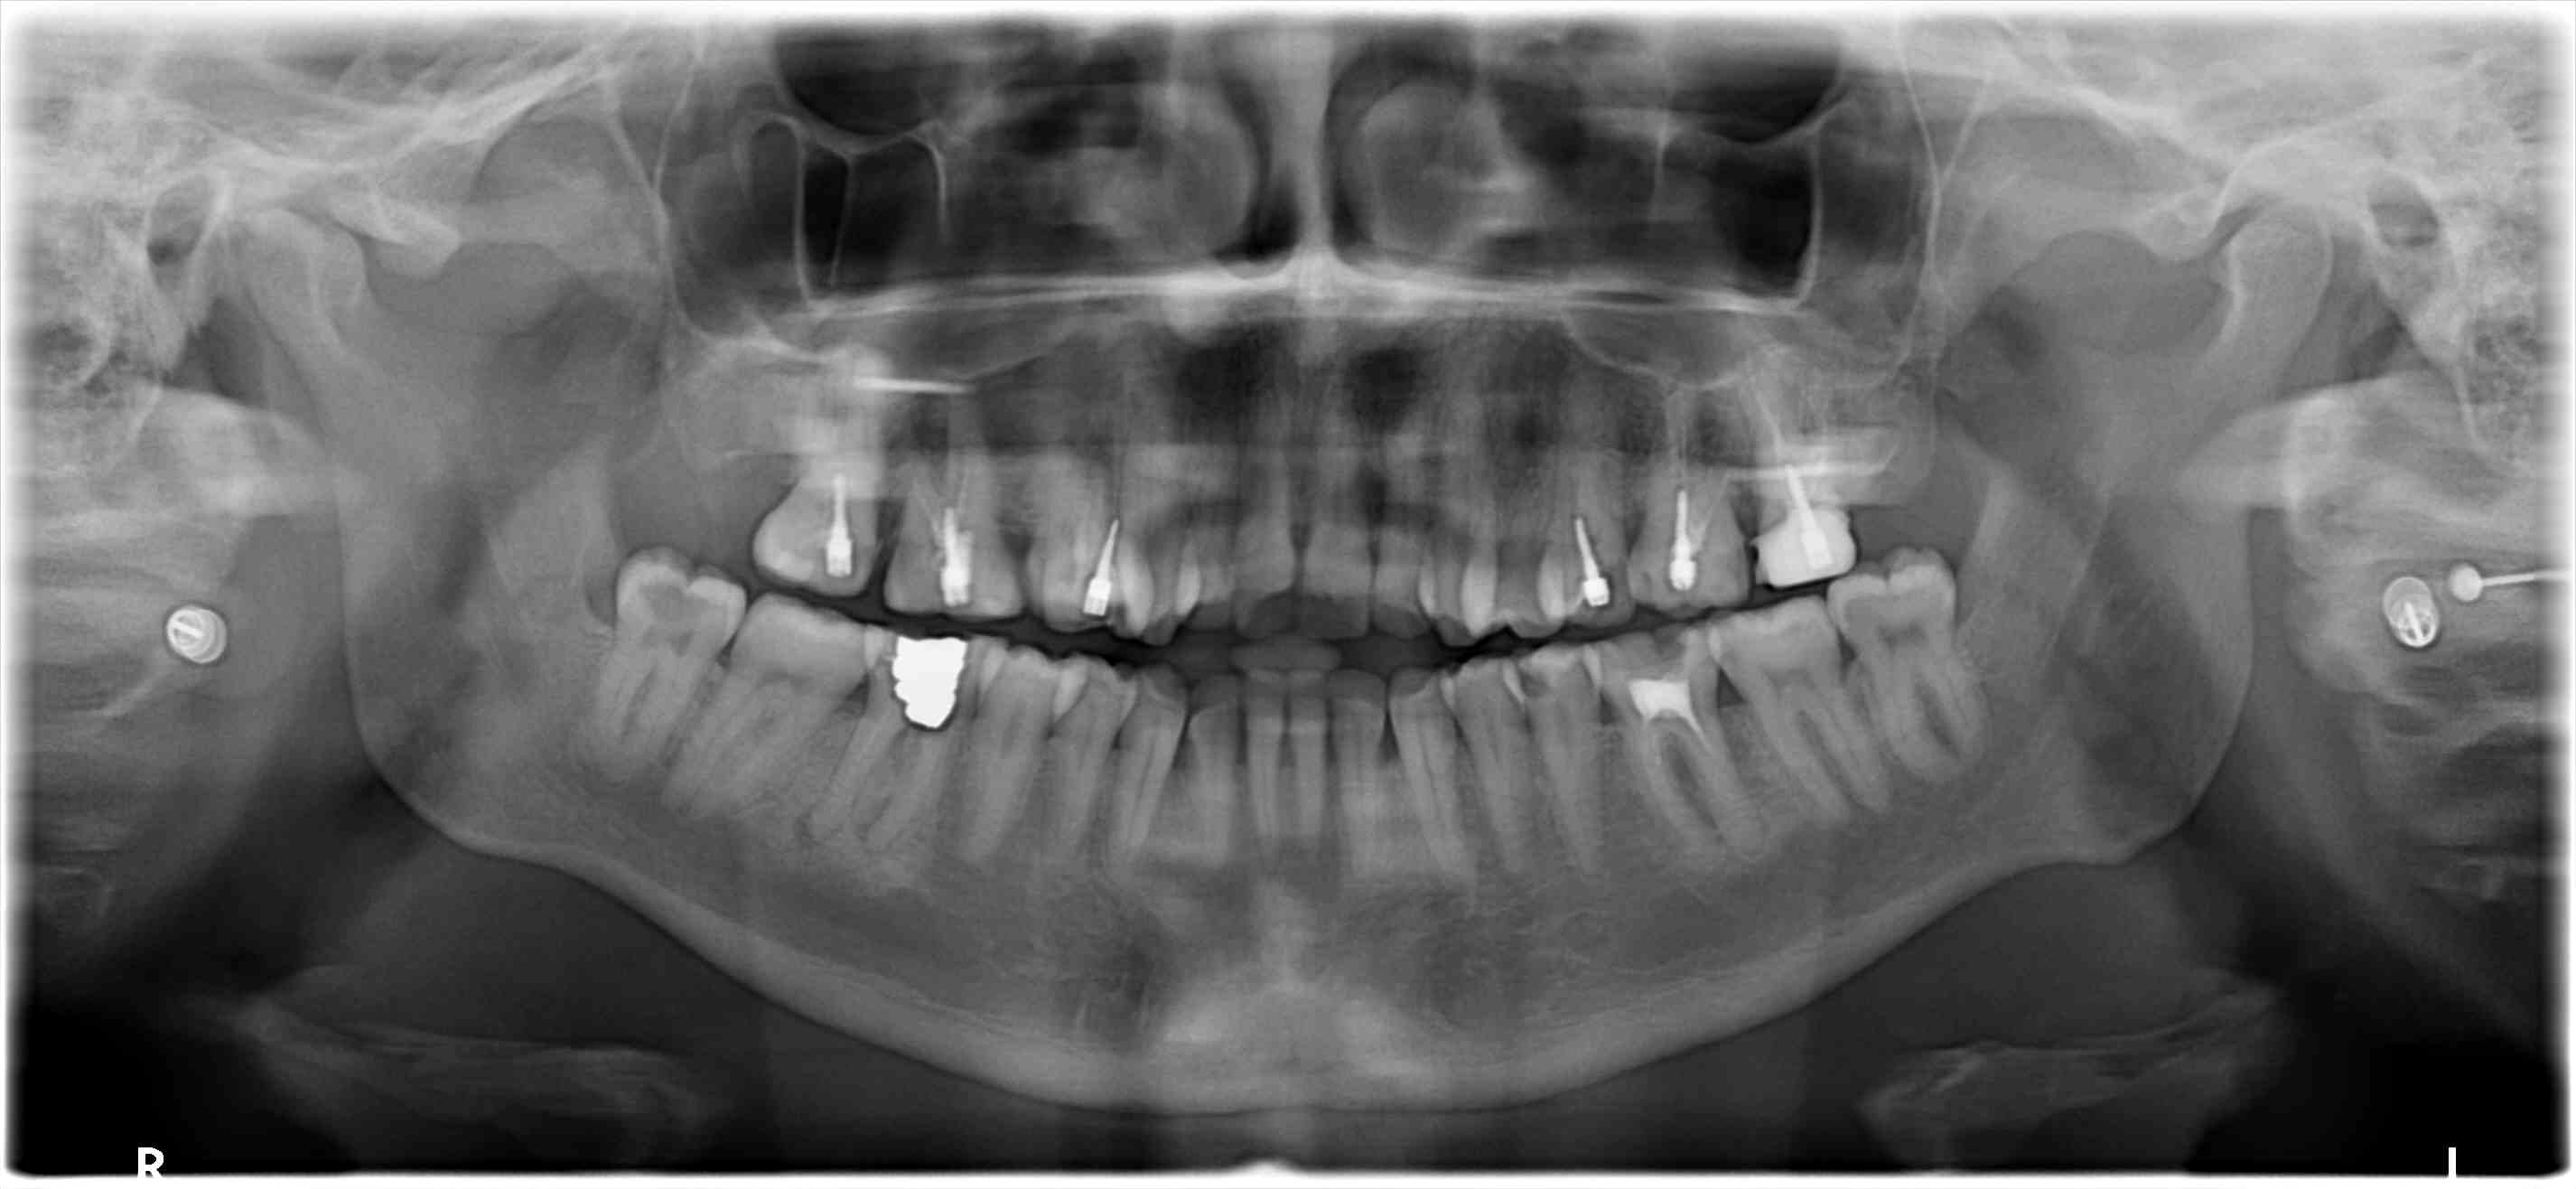

Tout frais!

Un CMU made in Roumanie, pour couronner ses dents qui se cassent, car il n'a pas confiance dans son pays.

burnax

20/09/2017 à 14h45

20/09/2017 à 14h50

burnax écrivait:

------

> Tout frais!

>

> Un CMU made in Roumanie, pour couronner ses dents qui se cassent, car il n'a pas

> confiance dans son pays.

moi je suis bien tenté de démarrer par la 46 . Au tri selectif !